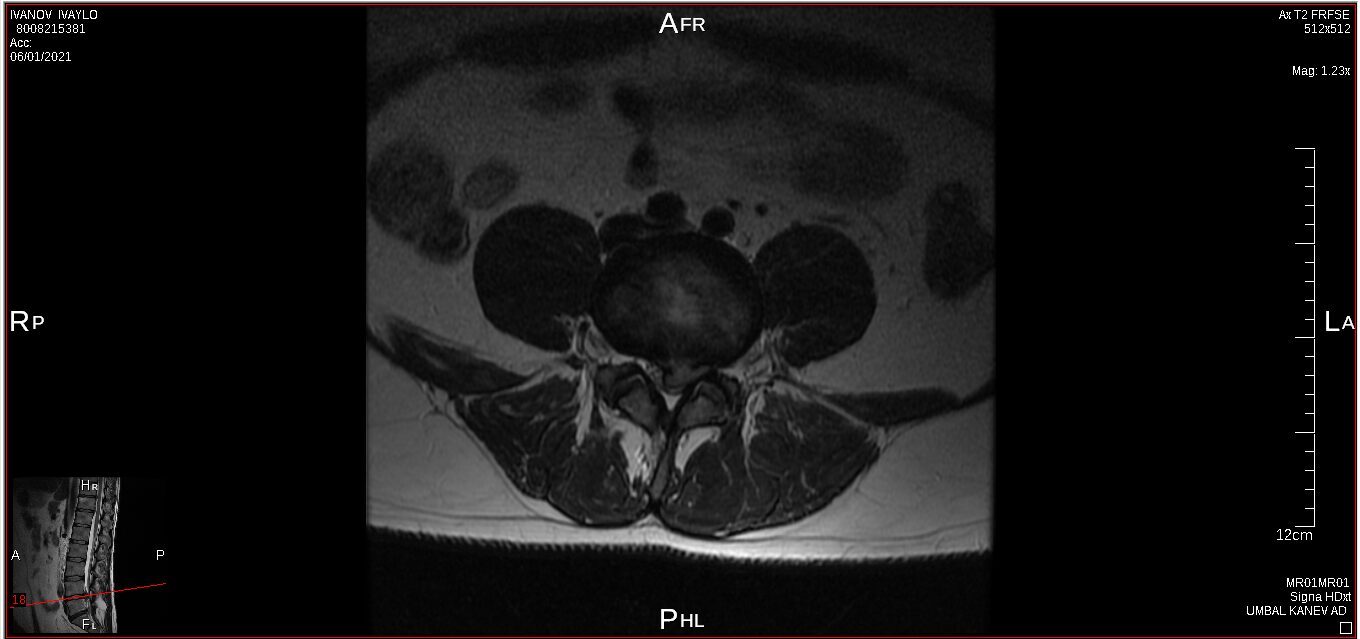

I have a lower spine problem, herniated disk and was using acupuncture (acupuncture is really good to control your musculus and controlling you like a robot) treatments with a Chinese doctor, first time all was perfect, but second time looks like happen mistake, you will be able to see this on pictures from private MRI scan– nuclear magnetic resonance that I have organised for myself. My left leg was just bone and skin, I lost all the musculus, because was not able to feed the main nerve responsible for keeping the proper function of the whole leg – I was parallelized. Pain is 24/7, 10 out of 10. At Royal infirmary hospital Edinburgh where I was hospitalized was giving me crazy amount of pain killers and very strong, that never helped. The doctors at the hospital they did great job providing me with modern technology to prevent the rest of the disk to slipping out to obtain the so-called calcification. All NHS staff did great job looking after me there. By 98% of the Doctors from around the world that I have managed to contact told me, that I have to make operation and there is no chance this to be sorted out other way. Well I have spent six months from my life and thanks god I had the finance to do that, trying to avoid operation. I have meet the right people to help me and expand my knowledge and I managed to avoid operation. Thanks to nature too. This situation get me to start learning a lot for human being anatomy and physiology, also reflexology, trigger points, blood, tocsins, minerals, how brain is responsible and reacting and much more…